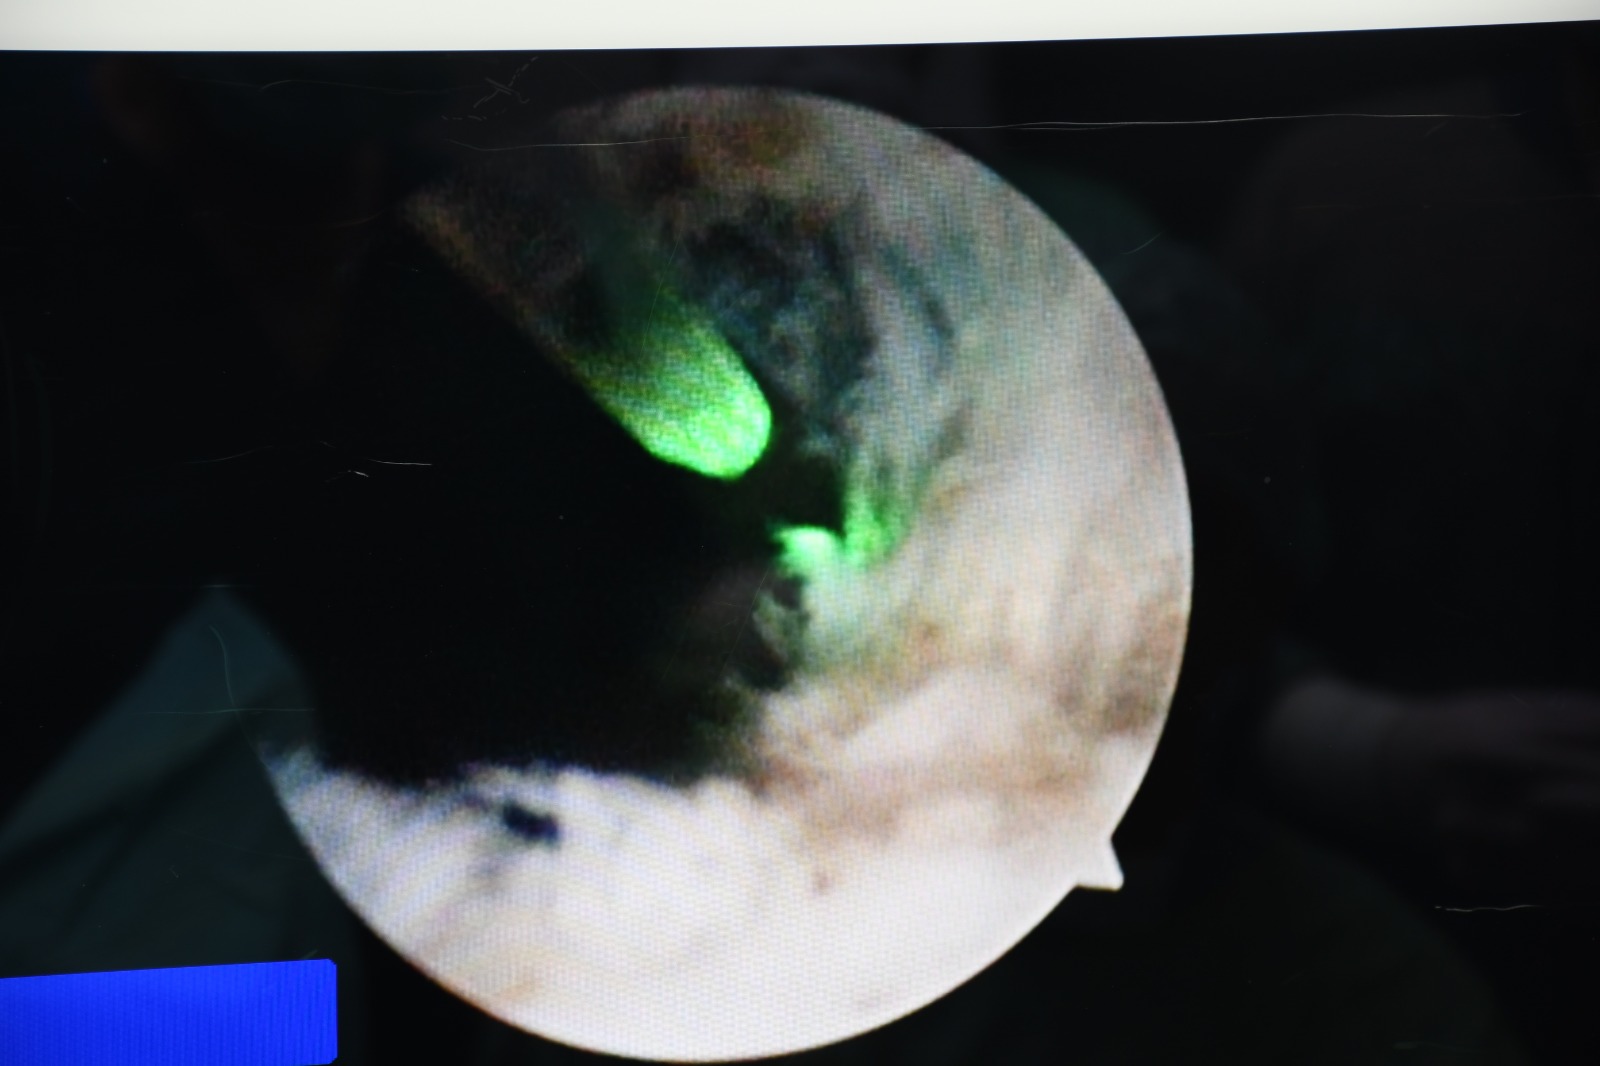

Hitit Üniversitesi Çorum Erol Olçok Eğitim ve Araştırma Hastanesi’nde ilk kez “HoLEP” (Holmium Lazerle Prostat Ameliyatı) yöntemiyle prostat ameliyatı gerçekleştirildi. Üroloji Kliniği tarafından alanında uzman hekimlerce yapılan operasyon başarıyla tamamlanırken, hasta sağlığına kavuştu.

HoLEP (Holmium Lazer Enükleasyon Prostat), iyi huylu prostat büyümesi (BPH) tedavisinde uygulanan kapalı (kesi yapılmadan) bir lazer ameliyatı yöntemidir.

Uzmanlar, HoLEP yönteminin klasik cerrahiye göre birçok avantaj sağladığını vurguluyor:

Daha az kanama

Daha az ağrı

Daha kısa hastanede kalış süresi

Günlük hayata daha hızlı dönüş

Büyük prostatlarda dahi yüksek başarı oranı

Yetkililer, iyi huylu prostat büyümesinin özellikle ileri yaş erkeklerde yaşam kalitesini ciddi ölçüde düşürdüğüne dikkat çekerek, HoLEP sayesinde hastalara daha güvenli, konforlu ve uzun vadede etkili bir tedavi imkânı sunduklarını ifade etti.